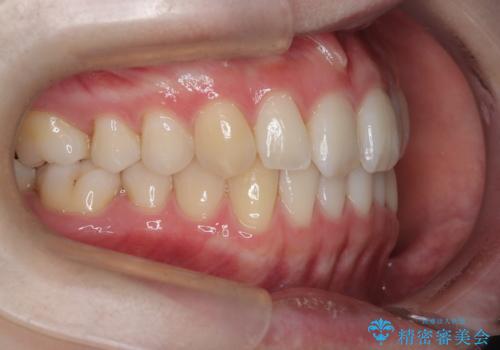

- 患者様は、前歯のガタガタ(叢生)と左下5番の欠損部が気になるとのことで来院されました。診断の結果、インビザラインを用いて前歯の叢生を整えながら、左下5番の欠損部にはインプラント治療を計画しました。矯正治療により、歯並びを改善すると同時に、噛み合わせのバランスも向上させることを目標としました。矯正期間とインプラントの治療計画を並行して進めることで、患者様のご希望に応えるプランを立てました。

前歯の叢生改善のため、インビザラインによる透明で目立たない矯正装置を使用しました。治療中は、歯の移動による負担を最小限に抑えつつ、歯列全体のバランスを考慮して進めました。左下5番の欠損部には、矯正終了後にインプラントを埋入し、自然で機能的な咬合を回復しました。治療期間中、患者様には装置の正しい装着と日々の清掃を徹底していただき、歯肉やインプラント周囲の健康を保つようサポートしました。結果として、美しい歯並びと快適な噛み合わせを両立させることができました。